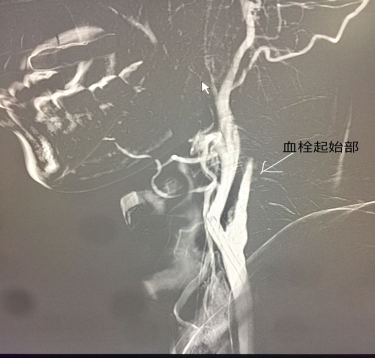

太极高手戴某,因为“突发言语含糊伴右侧肢体偏瘫三小时”到我院急诊,入院一小时后入导管室主动脉弓造影示右侧颈内鼠尾征-一起始部闭塞,左侧可见狭窄明显。

进一步右侧颈总动脉造影示典型鼠尾征